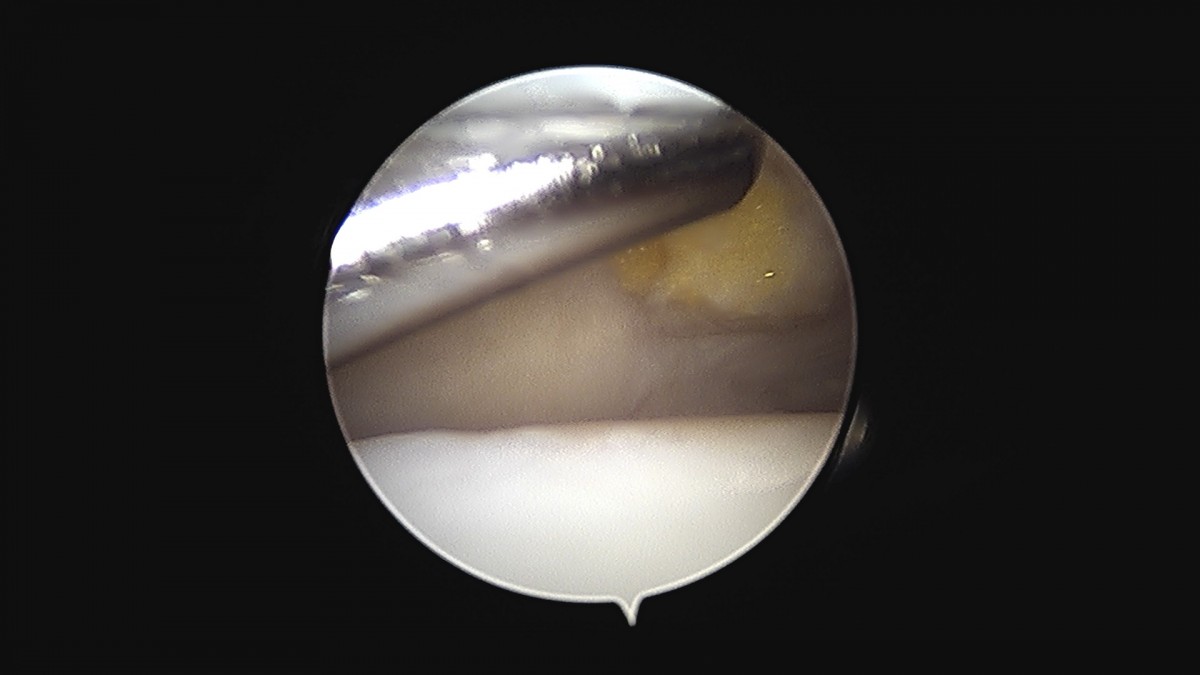

이재상원장님 무릎 변연절제술 권오O 환자

작성자 최고관리자 댓글 0건 조회 373회 작성일 25-09-16 16:11